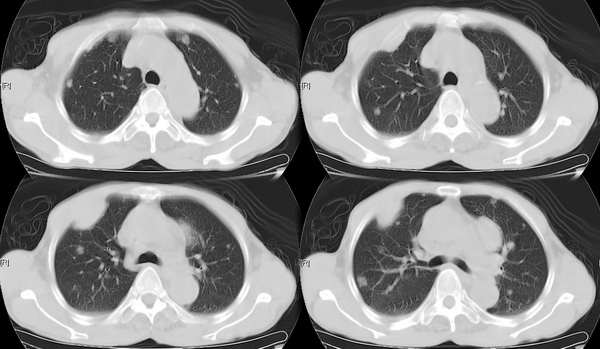

右颈部巨大软组织肿块影,范围较广,上至下颌角,下至颈静脉切迹。其最大层面位于右侧甲状腺区。肿块密度不均,其中有坏死液化区和班片状钙影,增强扫描见肿块实质区有强化。邻近结构挤压移位,部分结构侵蚀破坏,右侧多个颈深淋巴结肿大。两肺弥漫分布小结节影,以胸膜下为主,其大小不等,边缘光整。右侧胸壁亦见软组织结节影,纵隔多个淋巴结肿大及两侧锁骨上淋巴结肿大。

意见:右侧甲状腺癌并两肺、胸壁、纵隔淋巴结、颈深淋巴结、锁骨上淋巴结等广泛转移。